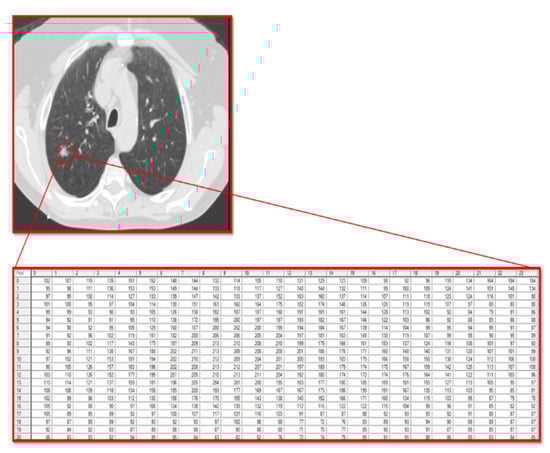

Malignancy in Ground-Glass Opacity Using Multivariate Regression and Deep Learning Models: A Proof-of-Concept Study

Background/Objectives: Ground-glass opacity (GGO) refers to areas of increased lung opacity on computed tomography (CT) scans. Distinguishing malignant from benign lesions using CT scans remains significantly challenging. This study aims to compare the performances of a linear multivariate statistical regression and an AI deep learning method in their abilities to predict GGO malignancy, given a set of pixel features extracted from CT scans. Methods: This retrospective study investigated patients from the Carmel Medical Center with findings of GGO nodules in their lung CT scans. Forty-seven consecutive patients were found to have either pure or part-solid GGO lesions, as defined by two independent radiologists. After manually segmenting the GGOs in the CT scans, pixel features were extracted using the MaZda software package, which analyzes six different image texture features. These textural variables were then compiled as input for the multivariate statistical regression. Additionally, an AI deep learning method, developed by our group and hosted on the cloud, was applied to the CT images containing the GGOs. Results: Among the 47 patients, 32 were diagnosed by pathology with malignant lesions and 15 with benign findings. Using the multivariate statistical regression, we identified 19 variables with statistically significant or near-significant differences through univariate analysis. In subsequent multivariate analyses, two independent variables that could distinguish between benign and malignant GGO lesions were identified: S(4,4)AngScMom (p = 0.012) and WavEnLH_s-2 (p = 0.008). The regression formula based on these two variables yielded a sensitivity of 91% and a specificity of 67% AUC: 0.8 (95% CI: [0.65, 0.94]). The AI deep learning model demonstrated a sensitivity of 100% and a specificity of 80% AUC: 0.96 (95% CI: [0.86, 1.00]). Conclusions: This proof-of-concept study demonstrates the superior performance of the AI deep learning model compared to the multivariate statistical regression, particularly in terms of sensitivity and specificity. However, given the small sample size, these results could potentially change with larger patient cohorts. Full article

Figure 1